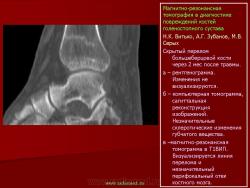

Магнитнорезонансная томография в диагностике повреждений костей голеностопного сустава.

Стрессовые переломы возникают при многократном давлении на кость с величиной, не достигающей критического значения, чтобы привести к острому перелому. Патофизиологически они обусловлены быстрой адаптацией мышц к нагрузке и недостаточной адаптацией к стрессу костей.

Семиотика стресс-переломов аналогична скрытым переломам костей голеностопного сустава и стопы. Дополнительно визуализируется периостальная реакция. Однако в отличие от скрытых переломов патологические изменения визуализируются и рентгенологически.